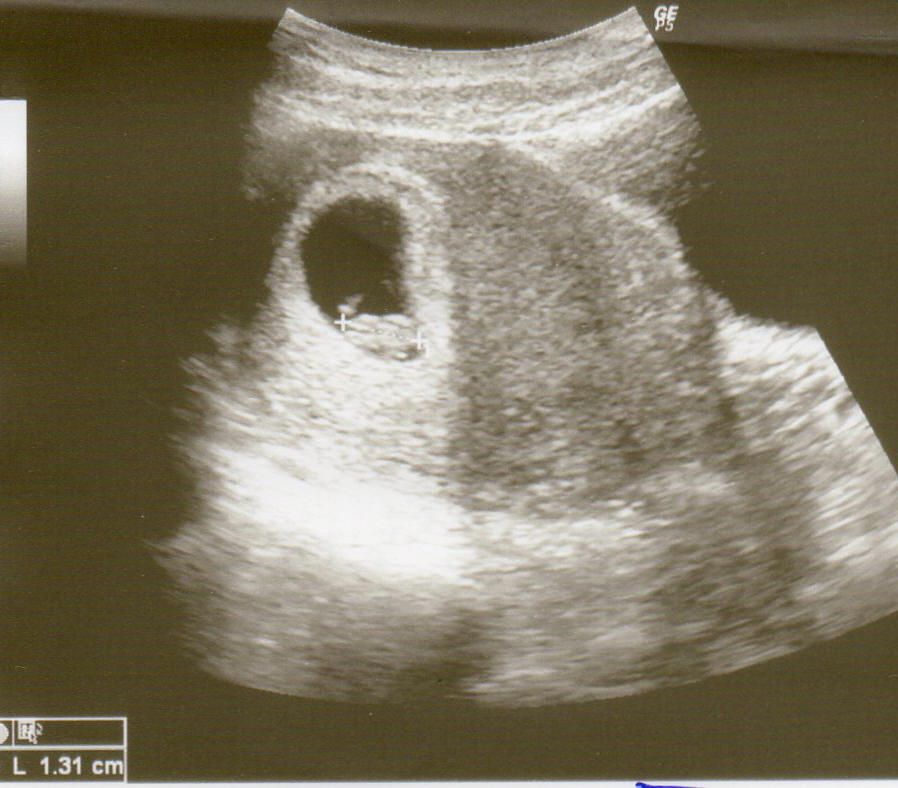

so jetzt versuche ich mal das Bildchen hochzuladen...

Ich bin jetzt bei 7+5. (wobei sich da Ärzte da um 2 Tage unterscheiden).